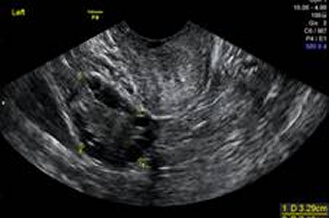

正常卵巢